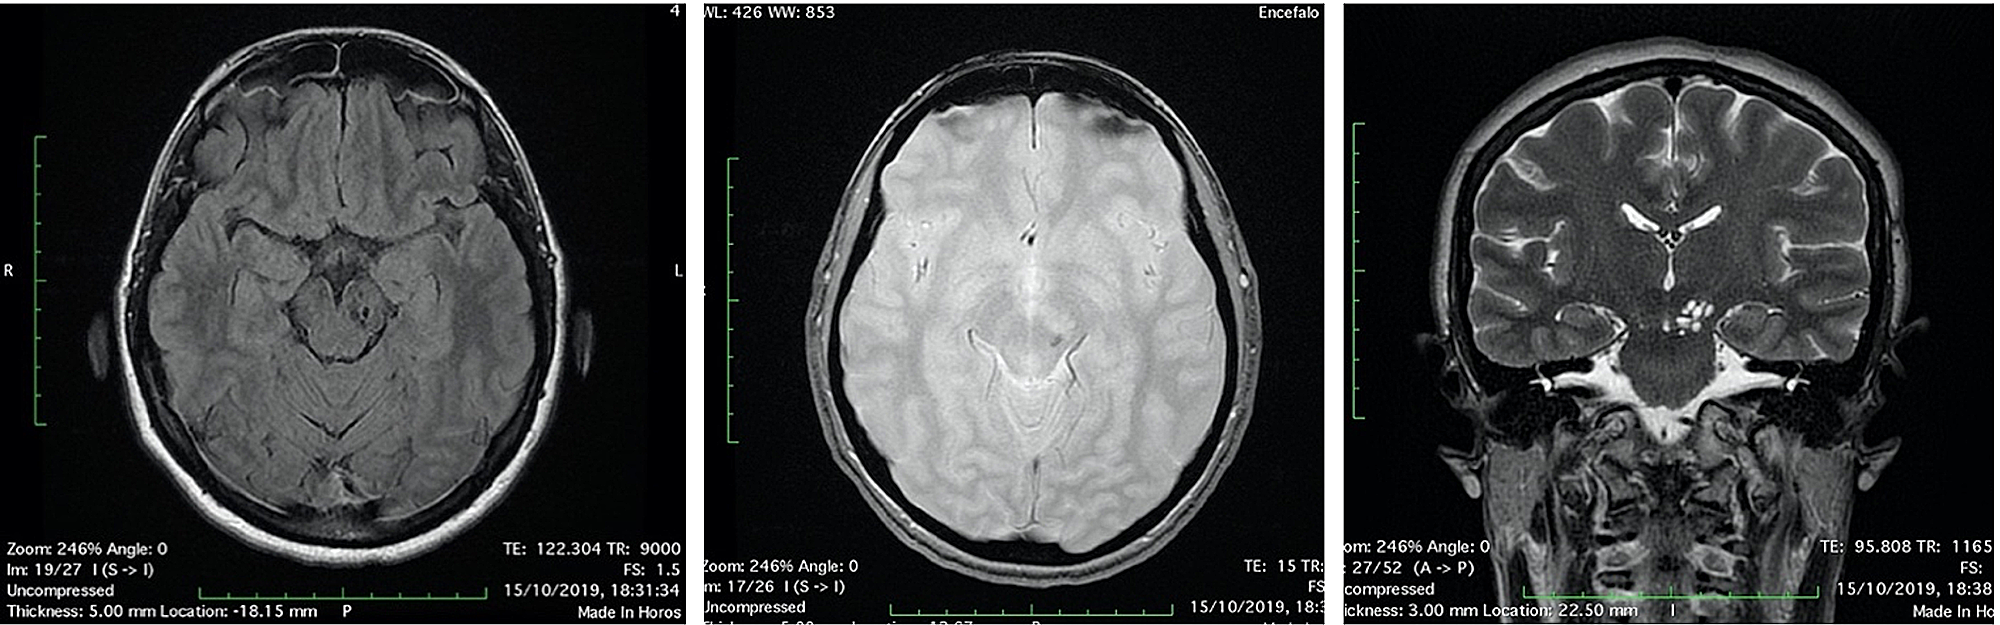

The first day after surgery, the patient was transfunded for hemoglobin 6.8 g/dL (normal range 12-16 g/dL), referring to scalp surgery. She complained headache, vertigo, nausea and diplopia, reflecting an involvement of the brainstem and the oculomotor nerves. A second CT and brain MRI with IV contrast were performed: CT scan showed a fluid-fluid level, with enlargement of left cerebral peduncle and a slight mass effect (Figure 2). MRI scan confirmed the same findings of fluid-fluid level, with enlargement of left cerebral peduncle and a slight mass effect; no contrast enhancement was observed: these findings were referred to enlargement of VRSs with post-traumatic bleeding. Neither SAH nor intracerebral hematomas were revealed (Figure 3). No neurosurgery was indicated but only clinical and imaging follow up.

Two days after the surgery, diplopia and nausea were disappeared, vertigo persisted. The patient stayed six days more in hospital to follow the reconstruction of the scalp and to recover. Unfortunately, the patient had a reject of transplanted skin with necrosis and had to schedule a new surgery in a month later. Before discharge, a CT scan was performed in order to assess the midbrain lesion (Figure 4).

The patient was discharged and she continued the treatment for the scalp lesion and gradually recovered from vertigo. She repeated CT and MRI exams to follow the midbrain lesion up: a CT scan after one month (Figure 5) and a MRI scan after four months (Figure 6). A significant volume reduction of the midbrain lesion was observed.